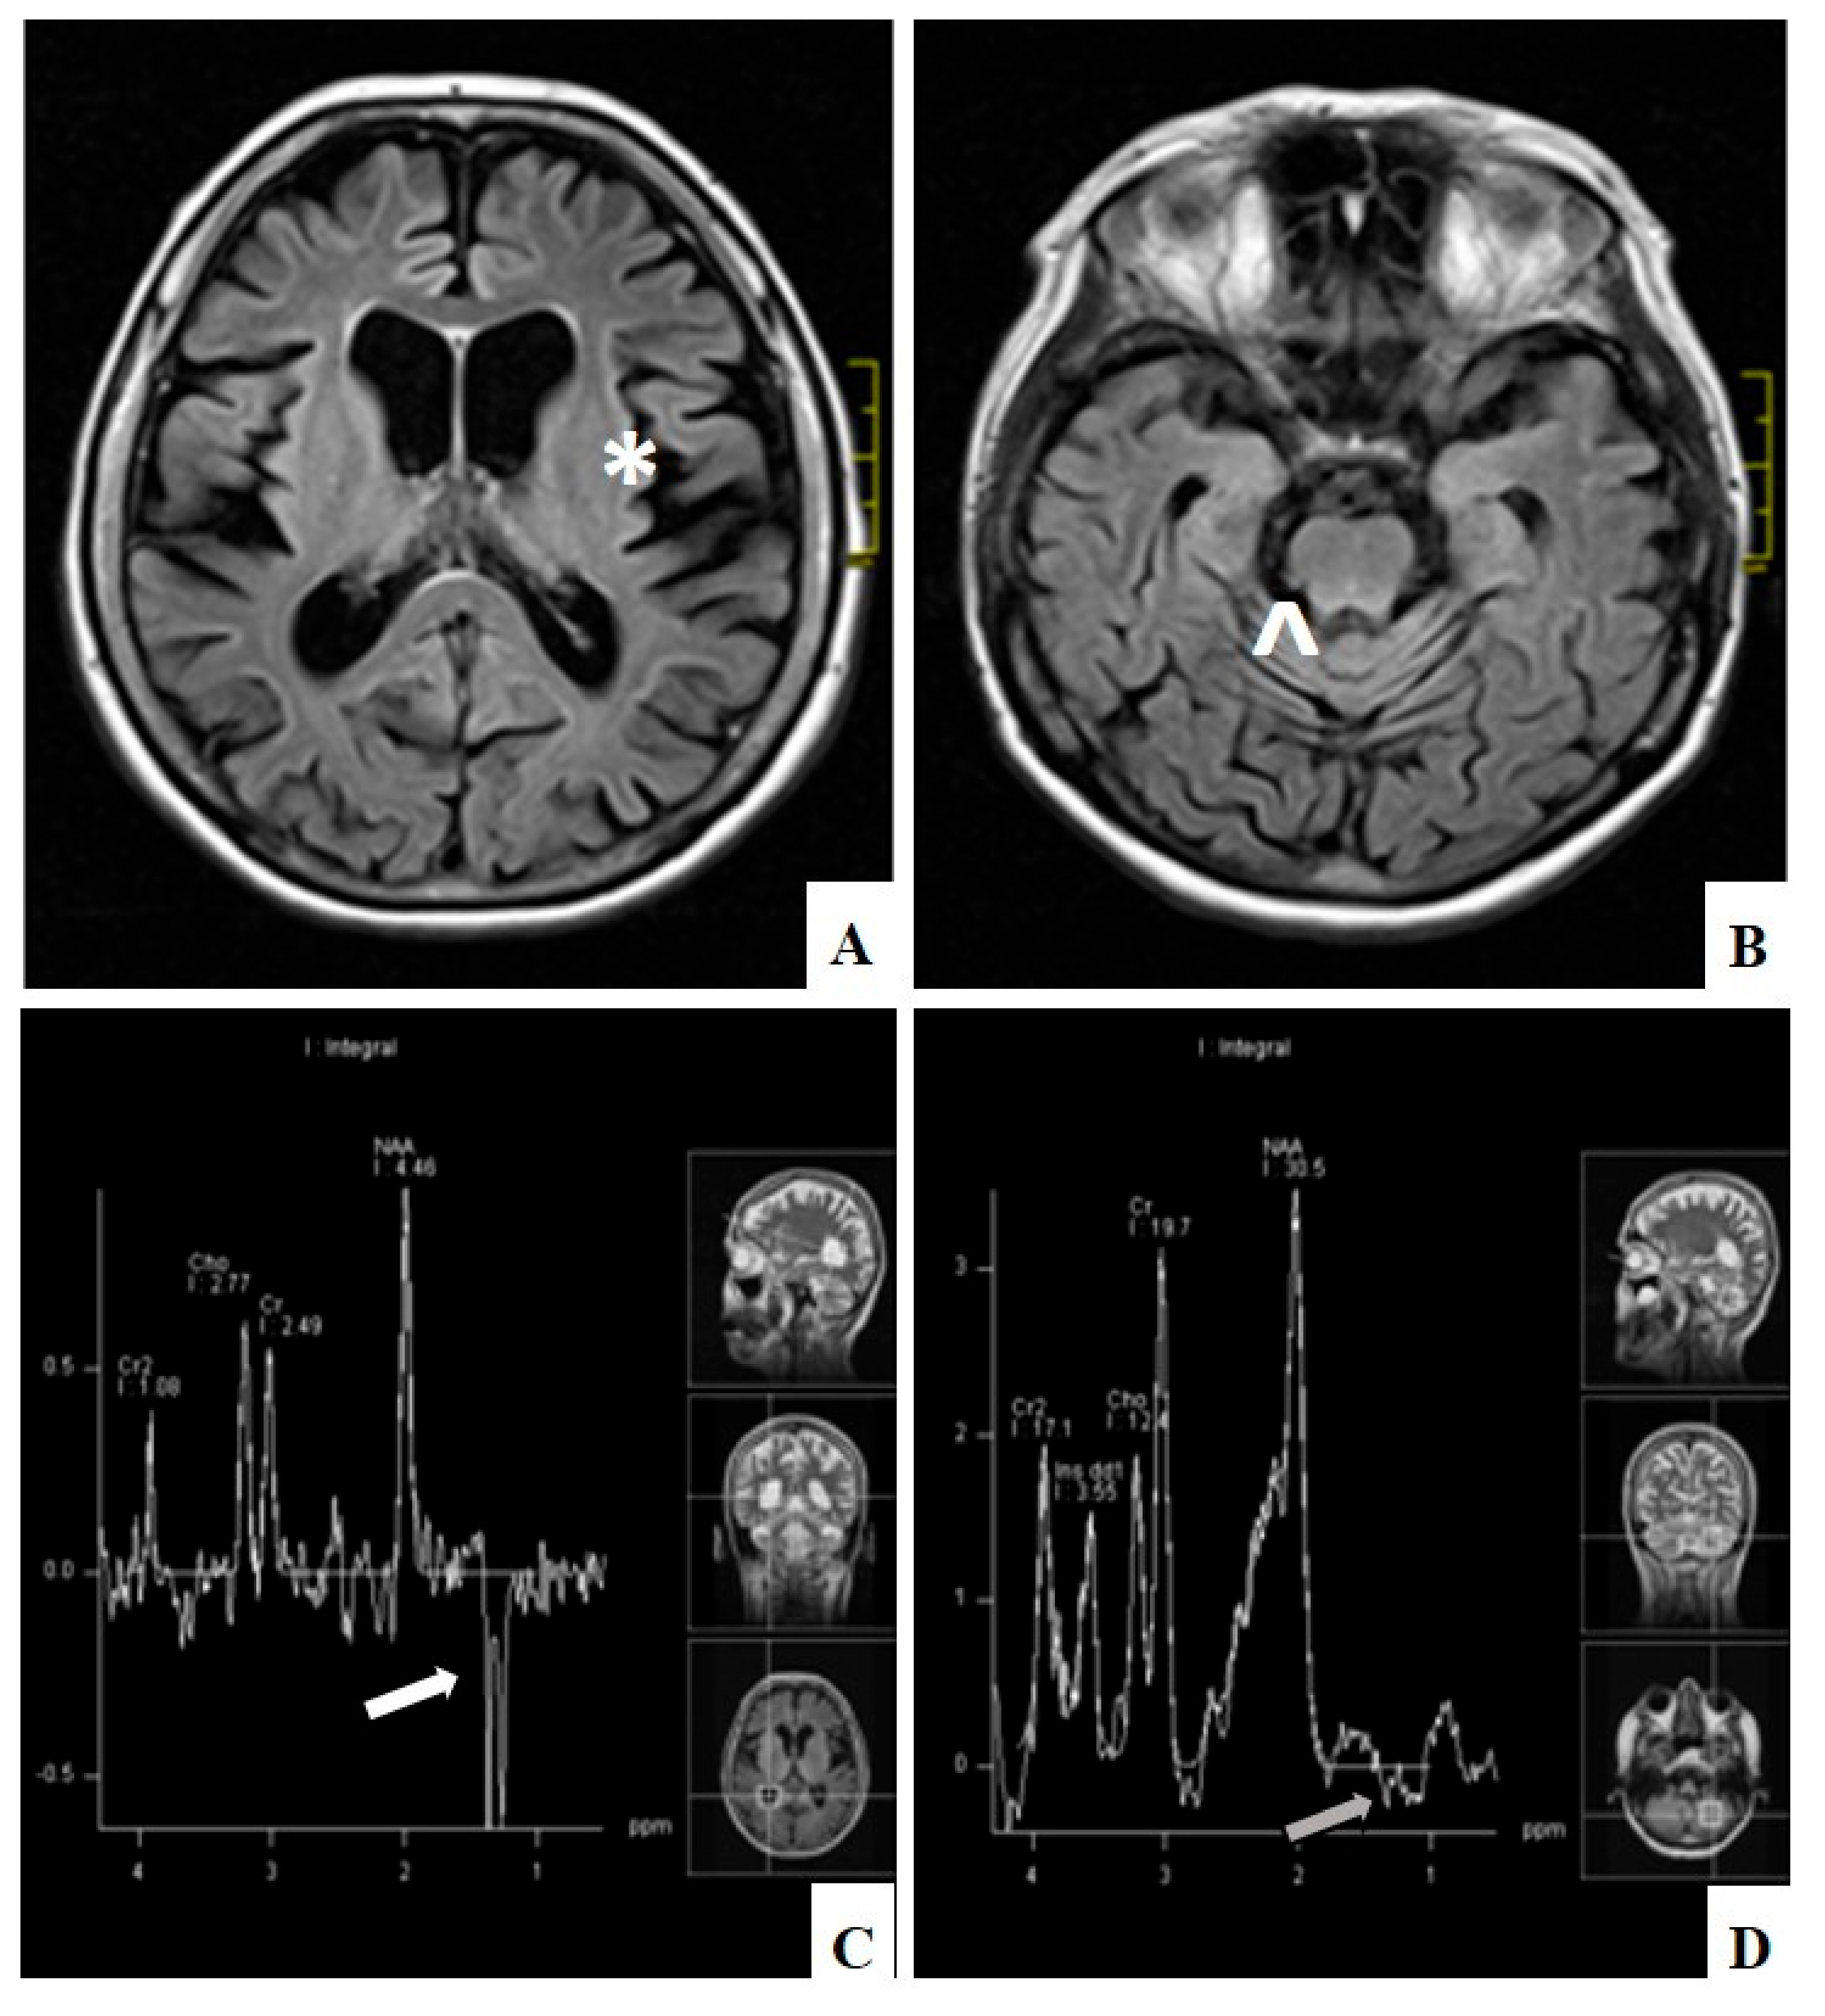

- Yu-Wai-Man, C.; Smith, F.E.; Firbank, M.J.; Guthrie, G.; Guthrie, S.; Gorman, G.S.; Taylor, R.W.; Turnbull, D.M.; Griffiths, P.G.; Blamire, A.M.; et al. Extraocular Muscle Atrophy and Central Nervous System Involvement in Chronic Progressive External Ophthalmoplegia. PLoS ONE 2013, 8, e75048. [Google Scholar] [CrossRef] [PubMed]